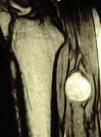

A todos los pacientes con enfermedad tumoral se les realizó además un estudio por resonancia magnética nuclear (RMN) previo a la cirugía, interpretado por el mismo radiólogo (LDF).

ResultadosRegistramos 12 schwannomas del nervio periférico, 9 en miembro superior y 3 en miembro inferior (tabla 1). En todos los casos la cirugía transcurrió sin incidencias, pudiendo resecar la tumoración del tronco principal del nervio, excepto en un caso donde tuvimos que sacrificar una rama solo sensitiva del nervio tibial posterior, una vez el registro neurofisiológico demostró que no tenía componente motor; en este caso quedó una hipoestesia residual en región gemelar interna (S2 según la clasificación del BMC), que duró 3 meses (figs. 2 y 3). Como secuela permanente, describimos un caso de schwannoma del nervio ciático poplíteo externo que comenzó con afectación sensitiva y motora (M1 y S1) (figs. 4 y 5), con una hipostesia en dorso del pie que persiste (S1 según la clasificación del BMC), aunque sin afectación motora. Registramos un caso de fibrolipoma del nervio mediano, también llamado hamartoma fibrolipomatoso neural, lipoma perineural o infiltración grasa neural, en un varón de 57 años que comenzó con clínica de síndrome de túnel carpiano y aumento de volumen de la cara volar de la muñeca. Pudimos tratarlo mediante sección del retináculo flexor de la muñeca y endoneurolisis del mediano. Por tanto, tenemos 11 casos de resultados excelentes y 2 buenos, uno con hipoestesia temporal y otro con recuperación motora casi completa aunque no sensitiva.

Encontramos hasta 3 publicaciones de aplicación de esta técnica en el caso de schwannomas del nervio tibial posterior como causa de síndrome de túnel tarsiano, dolencia que entra dentro del diagnóstico diferencial de las talalgias atípicas32–35. En 2 de las publicaciones se concluye recomendando la utilización sistemática de esta técnica para evitar lesiones yatrogénicas derivadas de la cirugía32,33. En nuestra serie, contamos con 3 schwannomas del tibial posterior, en todos los casos con recuperación completa y funcionalidad intacta (figs. 2 y 3).